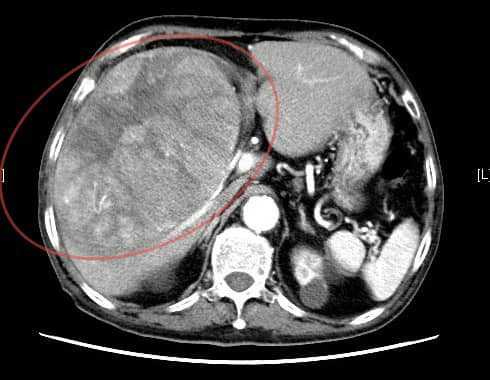

沒想到,阿公後來出現上腹疼痛和胃酸逆流,到錢政弘的門診就醫,「我聽他的描述和一般的胃痛的位置不太一樣,比較偏右上腹部,而且右側肋骨下方有壓痛,我初步懷疑是膽囊的問題,於是安排腹部超音波檢查,結果發現肝臟有一個15公分大的腫瘤,原先按壓會痛的地方其實是巨大的肝癌,直接可以用手摸到,後續CT檢查證實已經是晚期肝癌無法手術。」